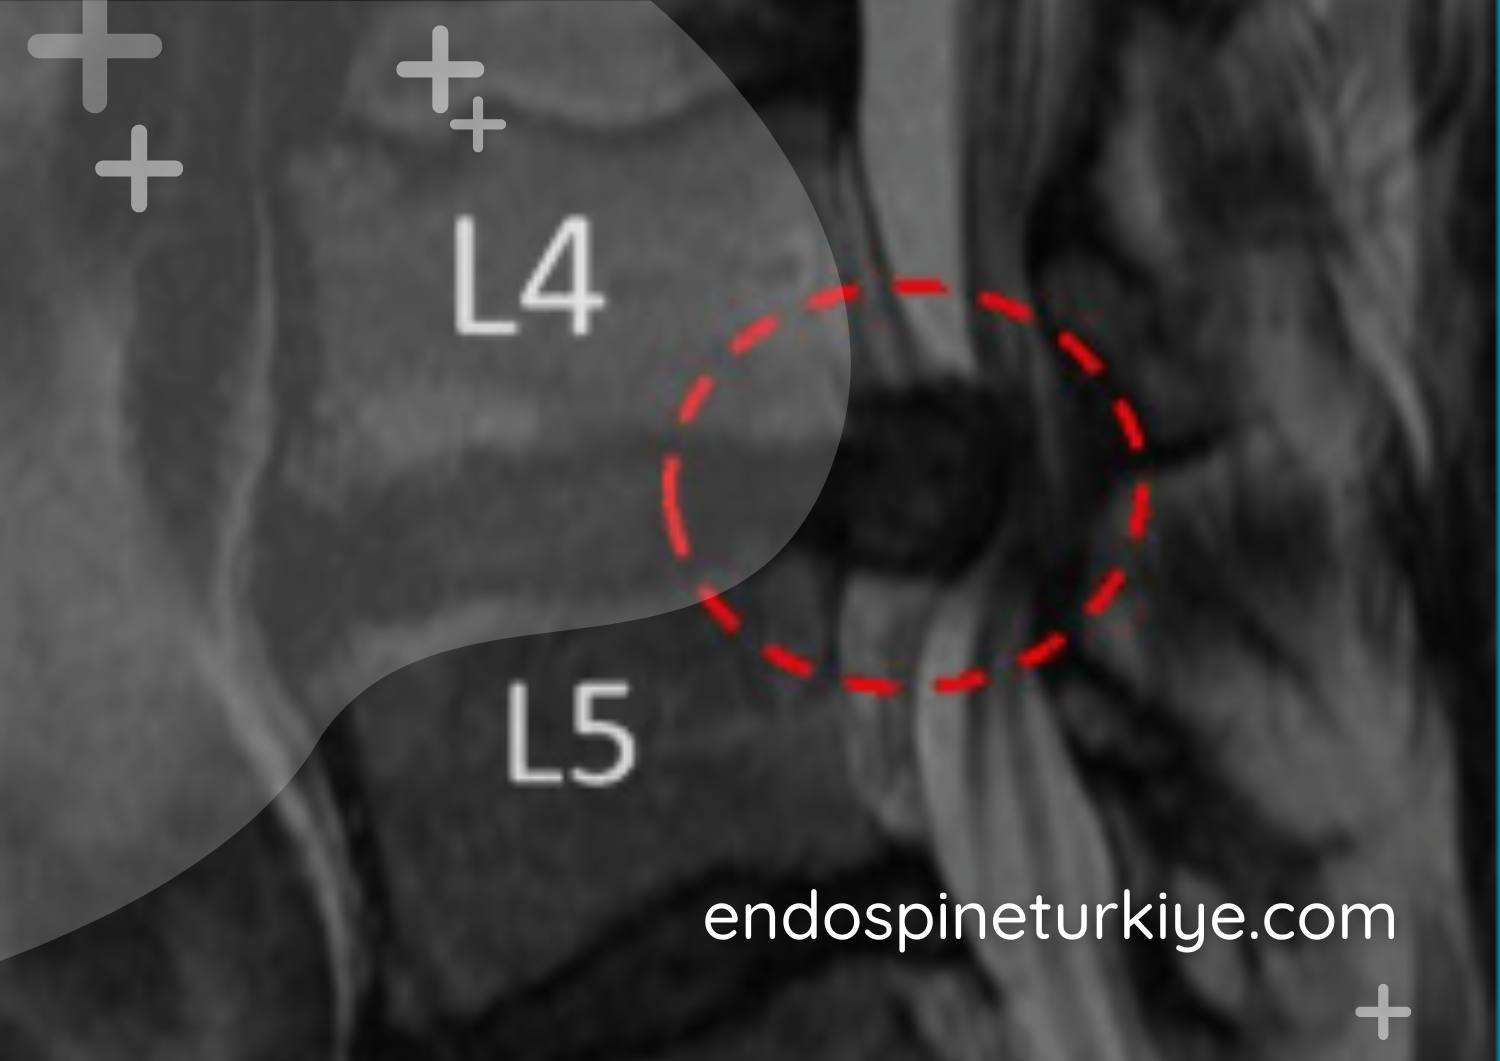

Omurga kanal daralması MR görüntüsü - Spinal stenoz teşhisi

Tedavi Öncesi

Daralmış spinal kanal